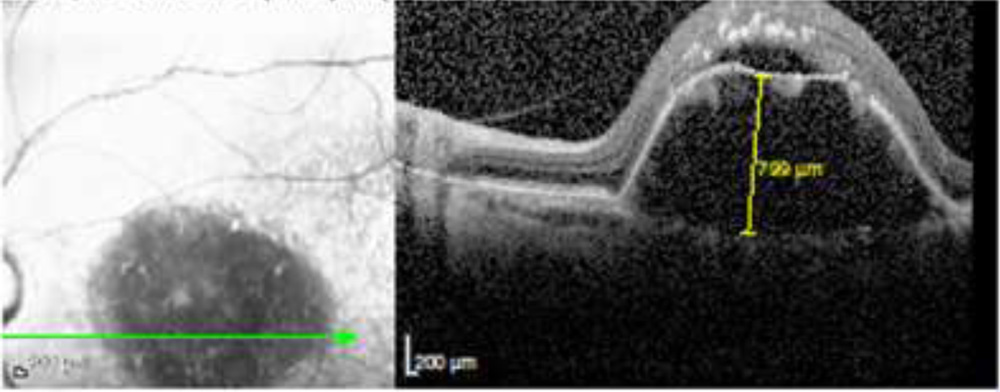

Figure 2 – Measurement of maximum vertical height of PED on SD-OCT

Figure 2 – Measurement of maximum vertical height of PED on SD-OCT

BCVA was evaluated at baseline and at last follow up with help of snellen’s visual acuity chart and later converted to LogMAR for calculation. Characteristics of PED observed in SD- OCT were location , maximal vertical height , type of PED and presence of notch in PED. PED height was measured manually with help of caliper provided inbuilt in Heidelberg software by measuring distance between RPE and Bruch’s membrane. And as per the critreriasmentioned by Dr Eichenbaum and colleagues in subgroup analysis of Harbor study PED with maximum vertical height of > 352 micron were considered as Extra large PED.5